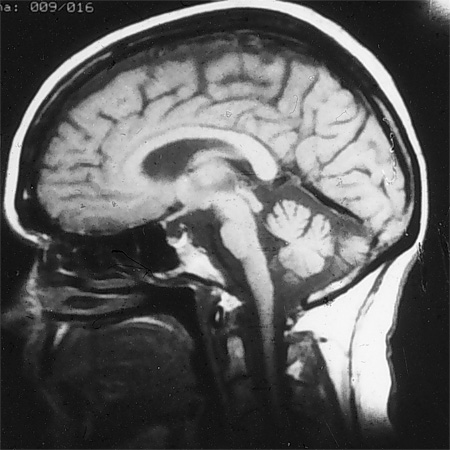

SCA 1-ს დრო ჩატარებულ თავის ტვინის მრი კვლევაზე ნაადრევად ჩანს ნათხემის და ტვინის ღეროს ატროფია

ექიმი ს.ჰ. საბრამონის კოლექციიდან; გამოყენებულია მფლობელის ნებართვით